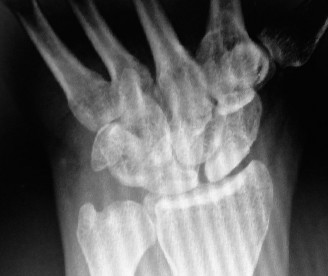

Imaging Studies:

- Standard Radiographs: AP, lateral, and oblique views of the elbow are mandatory. These identify osteophytes (especially coronoid and olecranon), loose bodies, heterotopic ossification, and malunion of previous fractures. The diagnostic significance of specific flexion limitations can often be traced to mechanical blocks visible on plain films.

- Computed Tomography (CT) Scan: Indispensable for complex post-traumatic deformities, significant HO, or when evaluating the precise location and extent of intra-articular impediments. 3D reconstructions are particularly useful for visualizing bony blocks to motion, such as prominent coronoid or olecranon osteophytes.